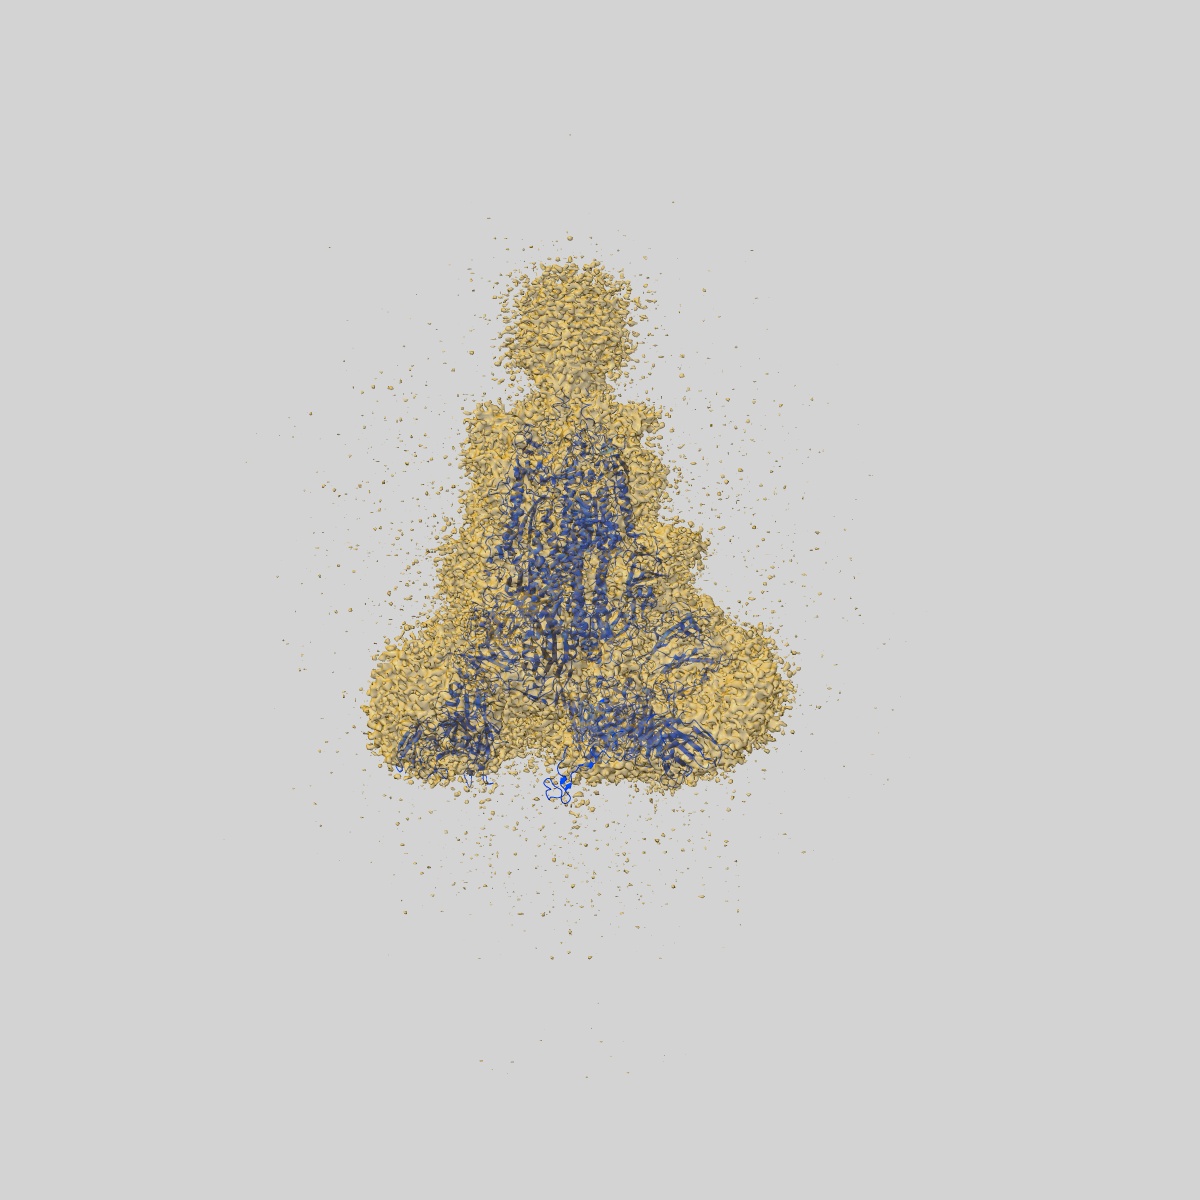

EMD-30333

SARS-CoV-2 S trimer with three RBD in the open state and complexed with three H014 Fab

Single-particle3.58 Å

Sample: SARS-CoV-2 S trimer with three RBD in the open state and complexed with three H014 Fab

Fitted models: 7cak

Structural basis for neutralization of SARS-CoV-2 and SARS-CoV by a potent therapeutic antibody.